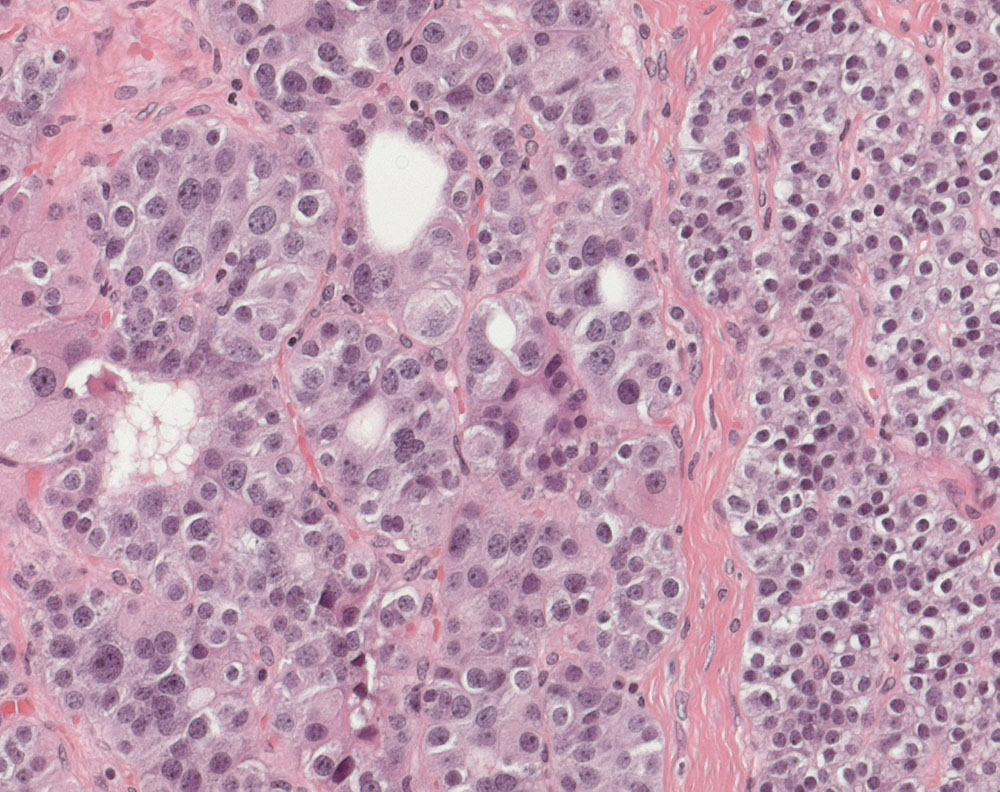

Die Tumorzellen links im Bild zeigen eine hohe Kern-Plasmarelation und Makronukleolen. Die Zellen rechts im Bild zeigen die Morphologie von Hauptzellen.

Atypisches Adenom der Nebenschilddrüse mit schmaler Kapsel, breiten fibrösen Septen und ausgeprägten Zellatypien mit Makronukleolen. Gewicht: 3g. Max. Durchmesser: 13mm. Kein invasives Tumorwachstum. Kein Kapseldurchbruch. Keine Gefässeinbrüche. Keine Nekrosen. 1 Mitose auf 10 HPF. Proliferationsrate (Ki-67): <1%.

44 jährige Patientin. Primärer Hyperparathyreoidismus. Vergrösserte Nebenschilddrüse.

Die auffallend breiten Fibrosesepten und Zellatypien lassen differentialdiagnostisch an ein Nebenschilddrüsenkarzinom denken. Sichere Malignitätskriterien wie Metastasen oder infiltratives Wachstum in umgebendes Gewebe wie Schilddrüse, Ösophagus, Nerven oder zervikales Weichteilgewebe oder Metastasen liegen hier nicht vor. Weitere Merkmale eines Nebenschilddrüsenkarzinoms fehlen ebenfalls (Kapseldurchbruch, Gefässeinbruch, >5 Mitosen/10 HPF, Nekrosen). Atypische Adenome werden als Tumoren mit unsicherem Malignitätspotential angesehen. Bei vollständiger Entfernung ist der Verlauf meist gutartig. Das atypische Adenom ist die häufigste Differentialdiagnose des Nebenschilddrüsenkarzinoms.